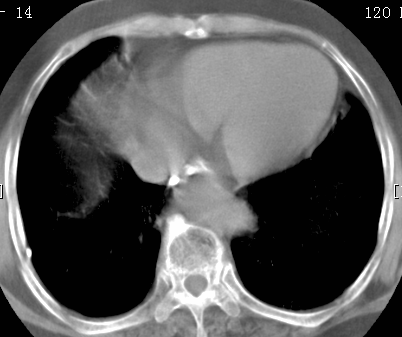

标题: CT26680:肺部右下肺静脉干结节的界定 [打印本页]

标题: CT26680:肺部右下肺静脉干结节的界定

经追查说有支扩咯血病史,但不确定

增强适应症

考虑1、周围型肺癌,2肺静脉畸形,前者可能大,建议增强检查。

考虑1、周围型肺癌,2肺静脉畸形,前者可能大,建议增强检查。支持!

不排除右肺下叶周围型肺癌可能。

中心型肺癌,纤支镜可帮助明确。